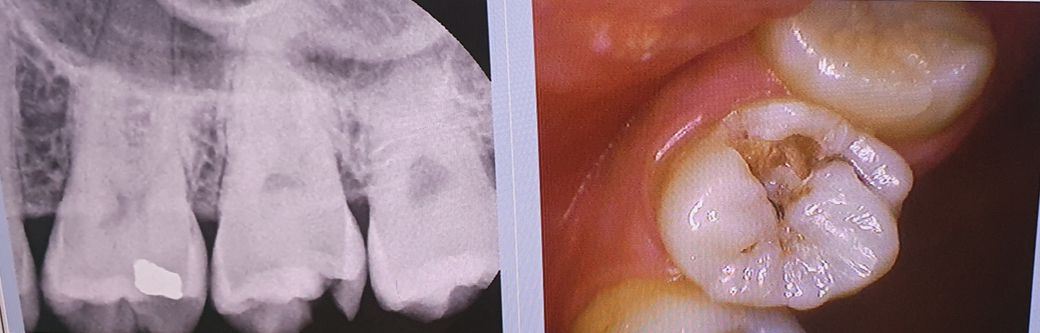

치아가 깨져서 치과에 가니 치아가 충치가 있어 신경치료를 해야한다고 하는데

통증은 없습니다 이럴 경우에 신경치료를 해야하나요?

• 1번 째 사진

x ray 사진상에서 충치가 치아 안쪽으로 깊이 진행되어 있습니다. 저 정도면 아마도 신경치료 해야 할 것으로 보입니다. 충치 다 제거하면 신경부위까지 근접하기 때문입니다.

사진으로만 봤을경우에는 충치가 신경관에 침범해 있는것으로 보입니다.

이런경우에는 충치를 제거하고 신경이 노출되기 때문에 일반적으로는 신경치료를 하게 됩니다.